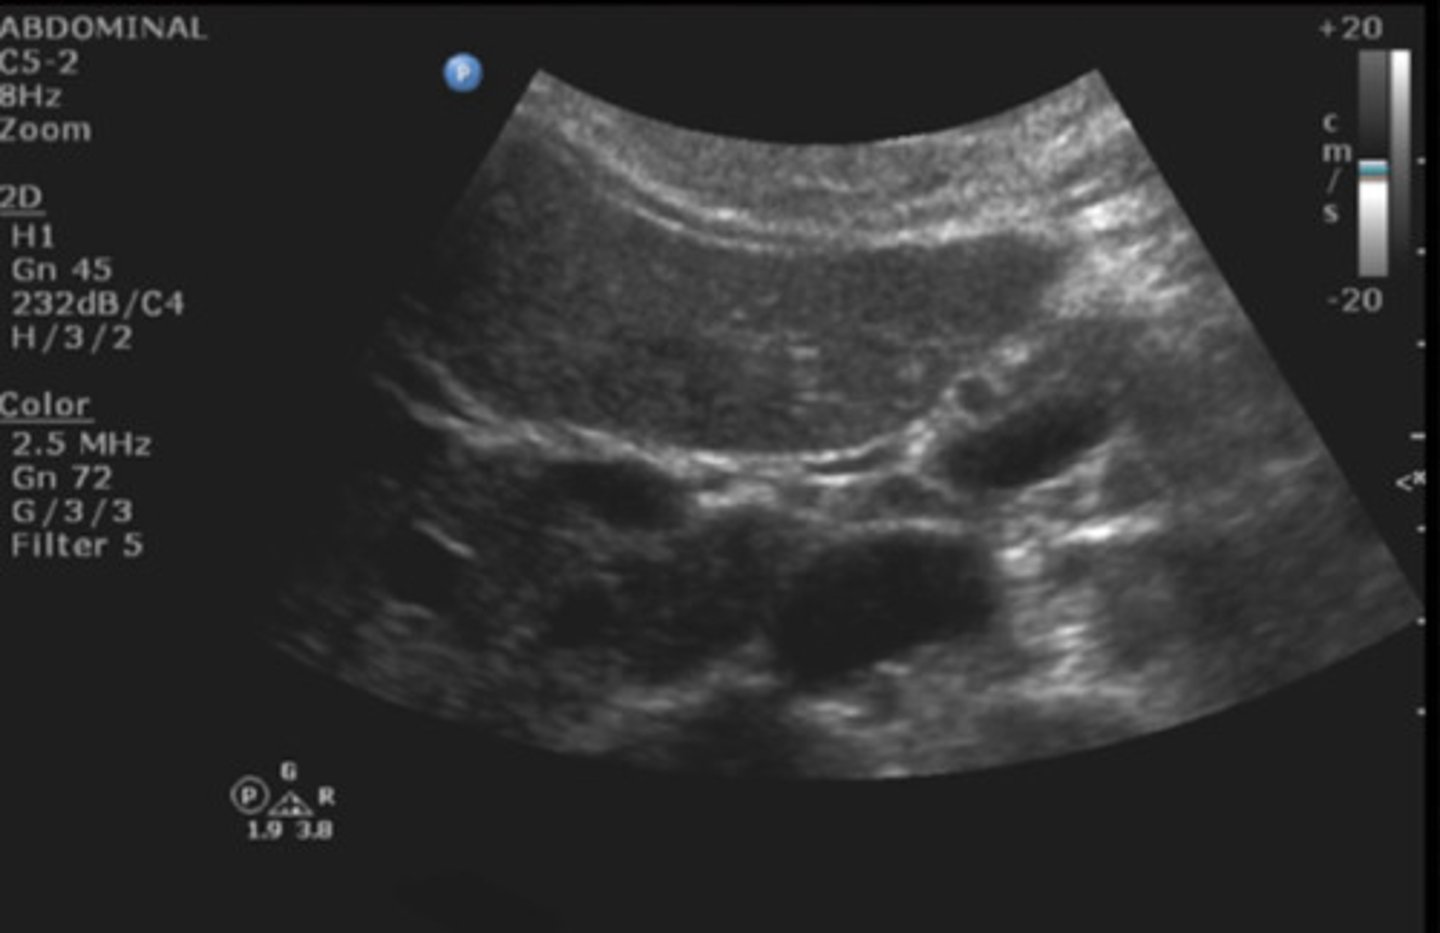

Portal triad

Identify the following;